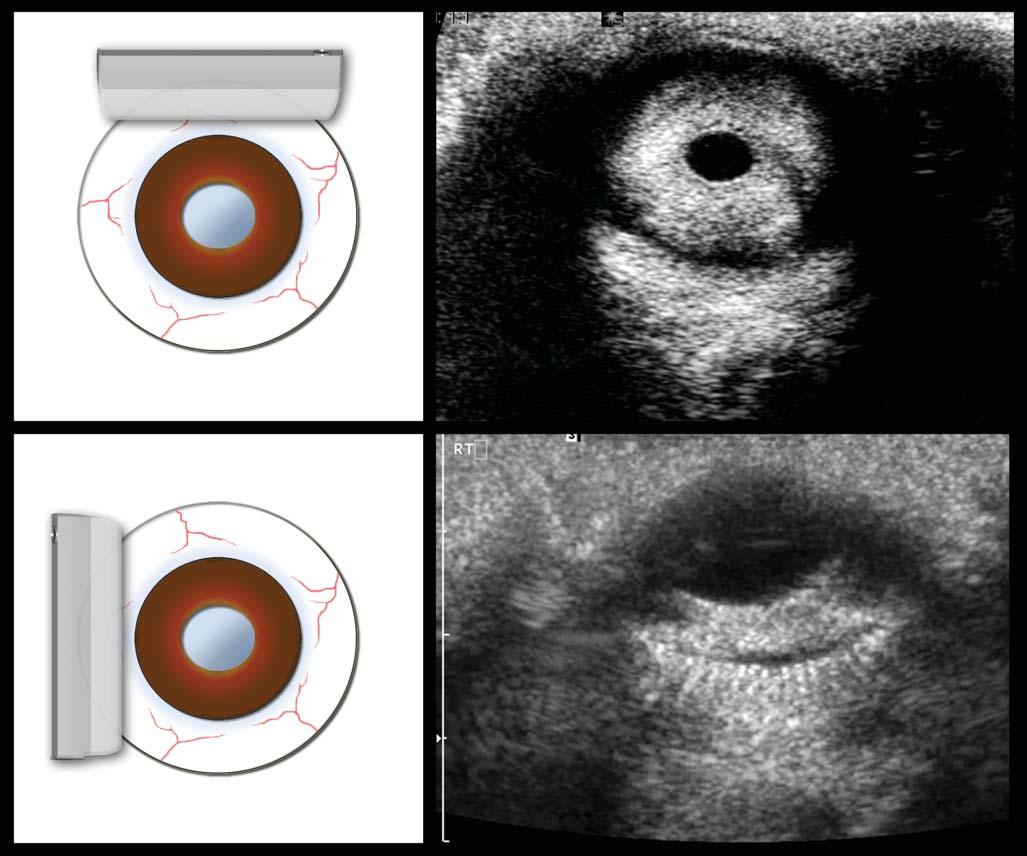

Ultrasoundprobes varyinconfigurationsforspecific needs(Figure1.4).Curvedlinearprobes,alsocalled convexormicroconvex,haveoneorseveralrowsof piezoelectriccrystalsalignedalongaconvexsurface, withvaryingbeamsandtracks.Theseprobesproduce

atriangularimagebecauseofthediverginglinesof ultrasoundwavestheygenerate.Themainassetsof thistypeofprobeareitssmallerfootprintanditslarge scanningfield,makingittheidealprobeforassessing theabdomen,particularlythecranialportionalong

theribcage.Thepiezoelectriccrystalsofthelinear probesaredistributedalongaflatsurface,producing arectangularscanfield.Thephaseintervalofthe impulsionscanalsoproduceatrapezoid-shaped image,allowingittocoveralargersurface.Thisis

Figure1.4. Practicalultrasoundtransducers. Mostultrasoundunitsareequippedwithconvex (A,B) andlinear (C) electronictransducerswithvariablefrequencies.Amacroconvexprobe (A) offeringlowerfrequencies(3–8MHz)isbestsuitedfor theabdomenoflargedogs,whereasamicroconvexprobe (B) ofhigherfrequencyandsmallerfootprintispreferredforthe abdomenofsmallpatientsandwhenonlyasmallacousticwindowisavailable(e.g.,theintercostalapproachofalunglesion). Ahigh-frequency(10–18MHz)linearprobe (C) ismostusefulforassessingsuperficialstructuresonarelativelywideandflat surface(e.g.,assessingbowelsinacat,bicepstendoninadog).Aphasedarraytransducer (D) offersasmallflatfootprintand isidealforechocardiography.

especiallyusefulwhenevaluatingsuperficialorgans whosediametermaybegreaterthanthewidthofthe scannedarea,suchasthekidneysandspleen.The lengthoftheprobe’sfootprintindicatesthewidthof theareaitscans.